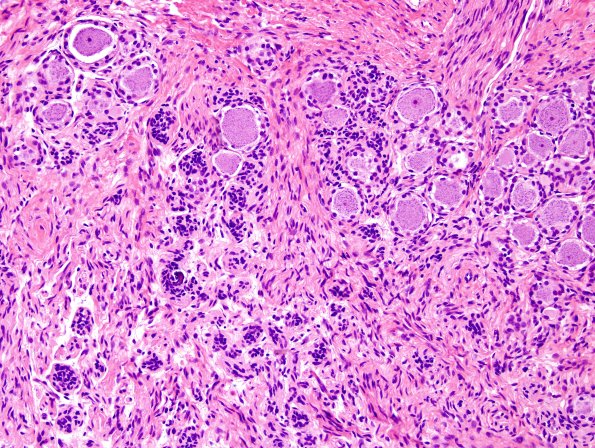

The DRG neurons are not chromatolytic; however, many have dropped out forming Nodules of Nageotte (satellite cell clusters forming by collapse after neuron loss). (H&E)